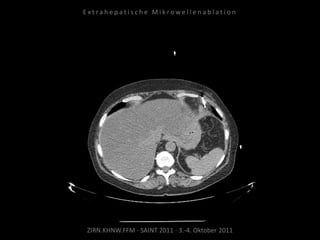

Verlaufskontrolle:

CT 24.06.2010

Regredienz des abladierten

Tumorgewebes.